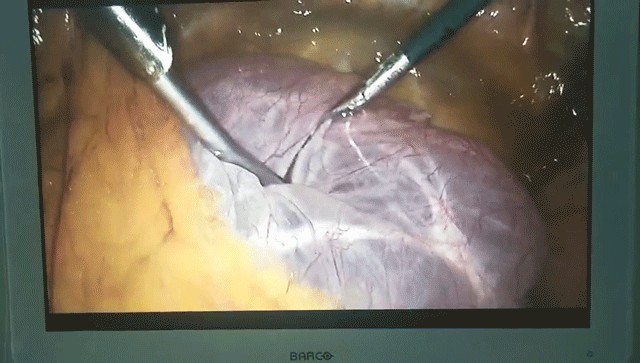

下腹部憋胀5年,发现盆腔肿物6天 专家诊室里,孔院长和多名妇产科临床专家一同会诊,悉心倾听患者的诉求,了解患者既往病史,分析原因,诊断病例病情,并给出有针对性的详细诊疗方案。 妇产科副主任医师白巧芳说:“作为赵阿姨的主管医师,我们一直密切关注患者身体各方面情况,考虑她年龄偏大,因为一直未曾定期体检,肿物直径也已经扩大到22cm,现在腹部膨大憋胀,行动乏力,在进行一系列相关检查,充分判断肿物来源、性质(良性还是恶性)等病情情况,经过充分的术前评估,考虑为来自于附件区的一个良性囊肿,与患者本人及家属多次沟通后,决定采用微创手术为其治疗。” 赵阿姨入院时,腹中盆腔肿物直径达22cm,经孔院长及妇产科专家联合会诊,5年前的她就自觉下腹憋胀,下蹲时候感觉更加强烈,但因为身在农村意识不够,再加上独自一人生活,担心给已经成家的女儿带来不必要麻烦,一直没有进行诊治,直到近两年下腹部明显增大,手触摸时发现有硬块,然而,身体负荷依然没有得到重视,赵阿姨每每想到心头的诸多顾虑,再一次选择了听之任之。直到上个月矿区进行老年体检时,B超检查才发现赵阿姨腹中的罕见巨大肿物。 了解既往病史,完善相关系列检查后,妇产科临床专家立即进行病情讨论,综合评估年龄、身体、心理等诸多因素的影响,一致认此次实施微创手术治疗,可以很大程度减轻患者对传统手术的恐惧性,创伤小,恢复快,而且后期疾病不容易复发。最终,制定了腹腔镜下微创手术方案,孔院长亲自主刀,在手术室医护人员的严密监测、密切配合下,为赵阿姨开展了腹腔镜下盆腔囊肿切除术,成功取出巨大肿物! 目前风险期基本过去,赵阿姨生命体征平稳,血压、脉搏都处于正常范围,家属对治疗结果非常满意,我们正在对她身体进行进一步的管理、观察。据悉,像赵阿姨身体出现的这种情况,盆腔肿物直径已扩大到22cm,是有很大风险性的,还好判断肿物为良性,风险处于可控阶段,若报告单为恶性,则会扩大手术范围......